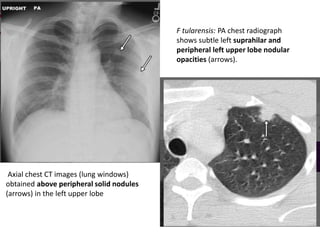

F tularensis: PA chest radiograph

shows subtle left suprahilar and

peripheral left upper lobe nodular

opacities (arrows).

Axial chest CT images (lung windows)

obtained above peripheral solid nodules

(arrows) in the left upper lobe

F tularensis: PAchest radiograph shows subtle left suprahilar and peripheral left upper lobe nodular opacities (arrows). Axial chest CT images (lung windows) obtained above peripheral solid nodules (arrows) in the left upper lobe